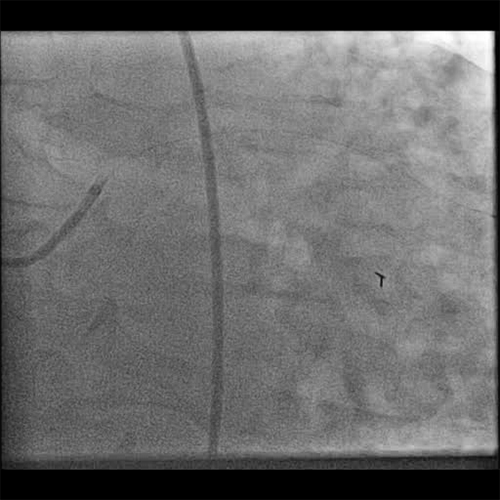

Diagnostic Angiogram

• Initial angiogram showed TIMI 3 flow

• Pre-wiring, the thrombus grade was 3

• The left main and left anterior descending arteries had no significant lesions

• The first obtuse marginal had a sub-total long thrombotic lesion in the proximal vessel (Cine 1: Diagnostic Angiogram)

• The RCA had a 70% proximal lesion and a 70% mid-vessel lesion